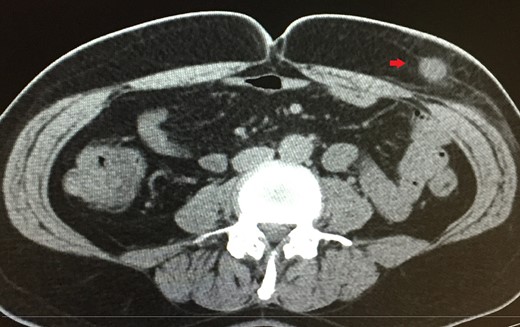

Clinical examination confirmed the mass, which was localized on the left midclavicular, subcostal and lateral to the umbilicus. It was palpable, firm with signs of tenderness. Laboratory tests were normal but clinical suspicion was high and so a computerized tomography (CT) scan with intravenous contrast (IV) was performed. This revealed a 1.8 cm × 2 cm lesion within the subcutaneous fat (Fig. 1), resembling an inflamed cyst.

A 1.8 cm × 2 cm lesion (red arrow) revealed in CT scan within the subcutaneous fat.